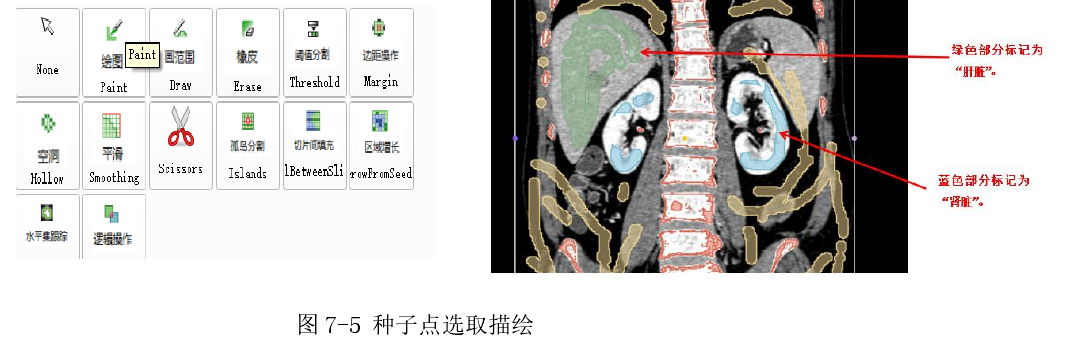

5.视图绘图工具

6.2.3 图像描绘与区域生长

如下图首先在图 7-5 左图中选择相应的描绘工具然后在切片视图中选取不同器官组织先标记为不同的颜色,之后就是选择相应的颜色后在图中标记种子点,为了分割出完整器官模型,需要选择一个颜色标记为对照区域(图中黄色部分),最后进行区域生长后产生效果如图(7-6)。如果出现了过生长或空洞的效果,则在分割基础上再选取一些种子点即可。